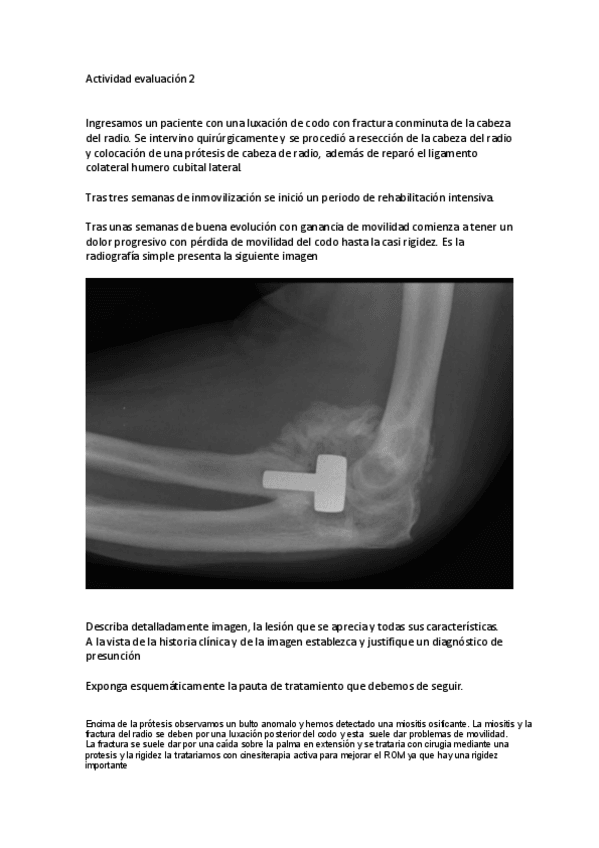

He publicado nuevos apuntes de 2º Afecciones médico-quirúrgicas I: Actividad-evaluacion-2.pdf

1 página